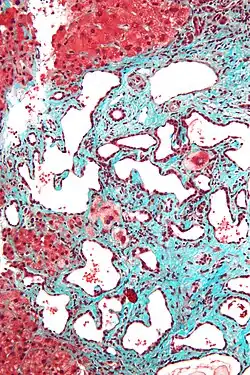

Micrograph of a bile duct hamartoma. Trichrome stain. Intermediate magnification

Micrograph of a bile duct hamartoma. Trichrome stain. Intermediate magnification -